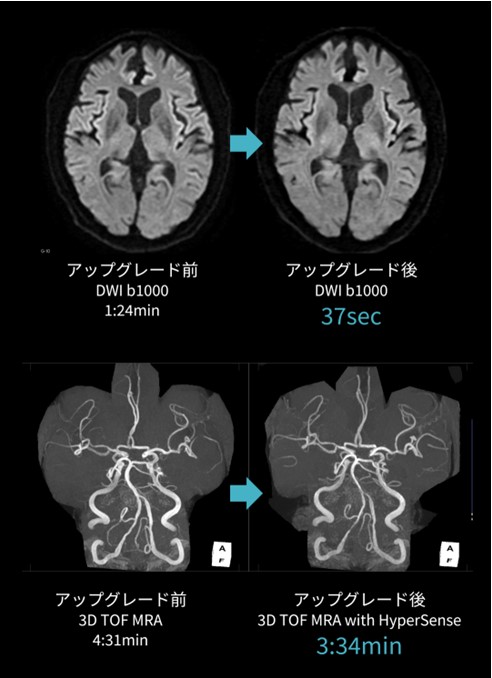

また、アップグレードによって新たに加わったアプリケーションにHyperSenseがある。HyperSenseは圧縮センシングの手法を用いて、SNRを損なわず撮像時間の短縮を可能とする技術で、3Dシーケンスに使用することができる。頭部MRAと頸部MRAは、HyperSenseを使用することによって、画質の劣化を抑えて撮像時間の短縮が可能となった。

頭部ルーチンの一例として、アップグレード前後で撮像していた脳梗塞後のフォローアップの患者さんの画像を挙げる(図.2-1)。

DWIは加算回数を3から1回に減らしているが、ノイズは目立たず両者に差はないと考える。頭部MRAに関しても、HyperSenseとARCのfactorを適切に設定して撮像することによって画質の劣化はみられず、穿通枝の描出も以前と変わらない印象である。また、当院では頸動脈プラークの簡易検索のため、脂肪抑制併用のCube T1をCoronalで撮像している。アップグレード前よりもスライス厚を薄くすることでMPRでも観察しやすい画像となり画質向上につながった。撮像枚数の増加による撮像時間の延長はHyperSenseによって最小限に留めている。(図.2-2)。

図2-1.アップグレード前後における頭部ルーチン画像の比較